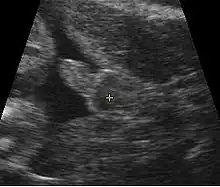

A gestational sac can be reliably seen on transvaginal ultrasound by 5 weeks' gestational age (approximately 3 weeks after ovulation). The embryo should be seen by the time the gestational sac measures 25 mm, about five and a half weeks.[10] The heartbeat is usually seen on transvaginal ultrasound by the time the embryo measures 5 mm, but may not be visible until the embryo reaches 19 mm, around 7 weeks' gestational age.[5][11][12] Coincidentally, most miscarriages also happen by 7 weeks' gestation. The rate of miscarriage, especially threatened miscarriage, drops significantly after normal heartbeat is detected, and after 13 weeks.[13]

Contents in the cavity of the uterus seen at approximately 5 weeks of gestational age

Artificially colored, showing gestational sac, yolk sac and embryo (measuring 3 mm as the distance between the + signs)

Embryo at 5 weeks and 1 day of gestational age (at top left) with discernible heartbeat

Embryo at 5 weeks and 5 days of gestational age with discernible heartbeat